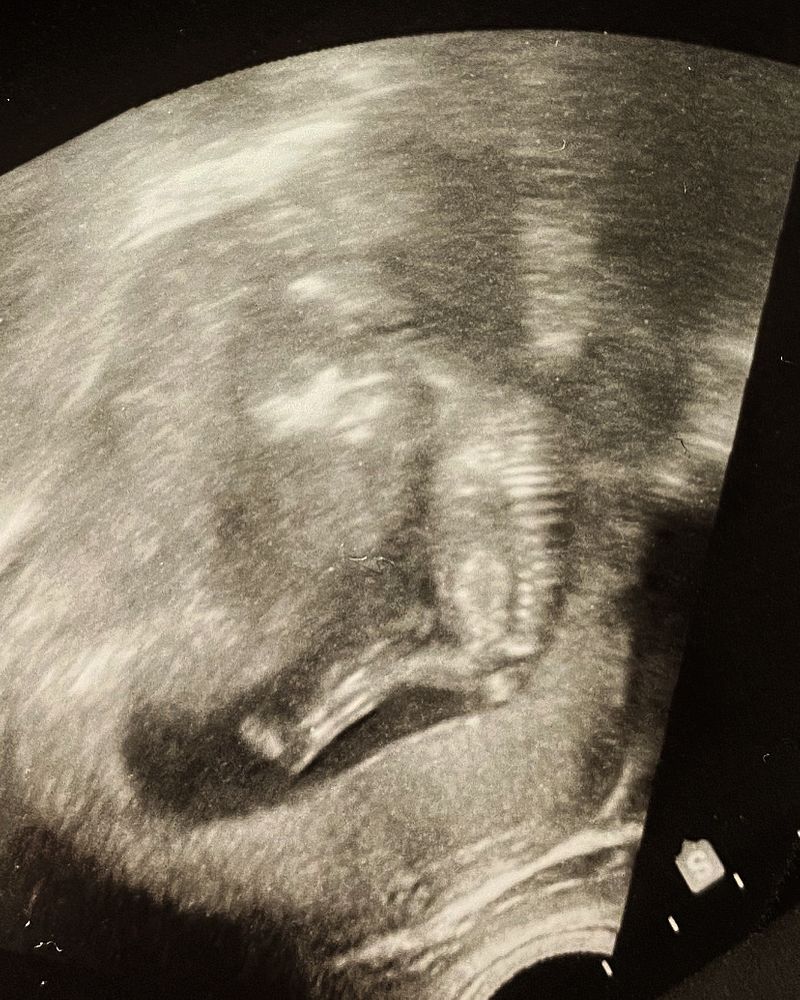

Сегодня моей кнопке 12 недель и 5 дней, вот и состоялась наша первая встреча! Я так переживала… особенно переживания усилились, когда врач-УЗИ смотрит и молчит. Тишина. Как будто нашла что-то плохое, но проверяет, чтобы в этом убедиться. Я, не выдержав, спрашиваю - а чего вы молчите?! А мне в ответ - а всё прекрасно, придраться не к чему. Все соответствует сроку, все без особенностей, то, что надо, визуализируется, ЧСС 158 уд/мин, КТР 68 мм. Предположить кто не могу и не буду, закрыл ножками интересное место. И лишь после всего сказанного повернула мне экран и показала малыша… включила послушать сердечко… и тут моя мамская сентиментальность не выдержала и я расплакалась от счастья и от того, что все хорошо. А малыш в это время стал сосать палец, на что медсестра (очень хорошая и общительная женщина, по сравнение с врачом) говорит - мать у нас голодная?! Говорю - ну да, кровь натощак надо было сдать… - Ааа! Оно и видно! Вон, есть хочет дитя! Палец в рот положил!

Когда дело дошло до фото, то человек не захотел общаться, перевернулся, уплыл куда-то далеко и оставил маме на память лишь такое фото.💕